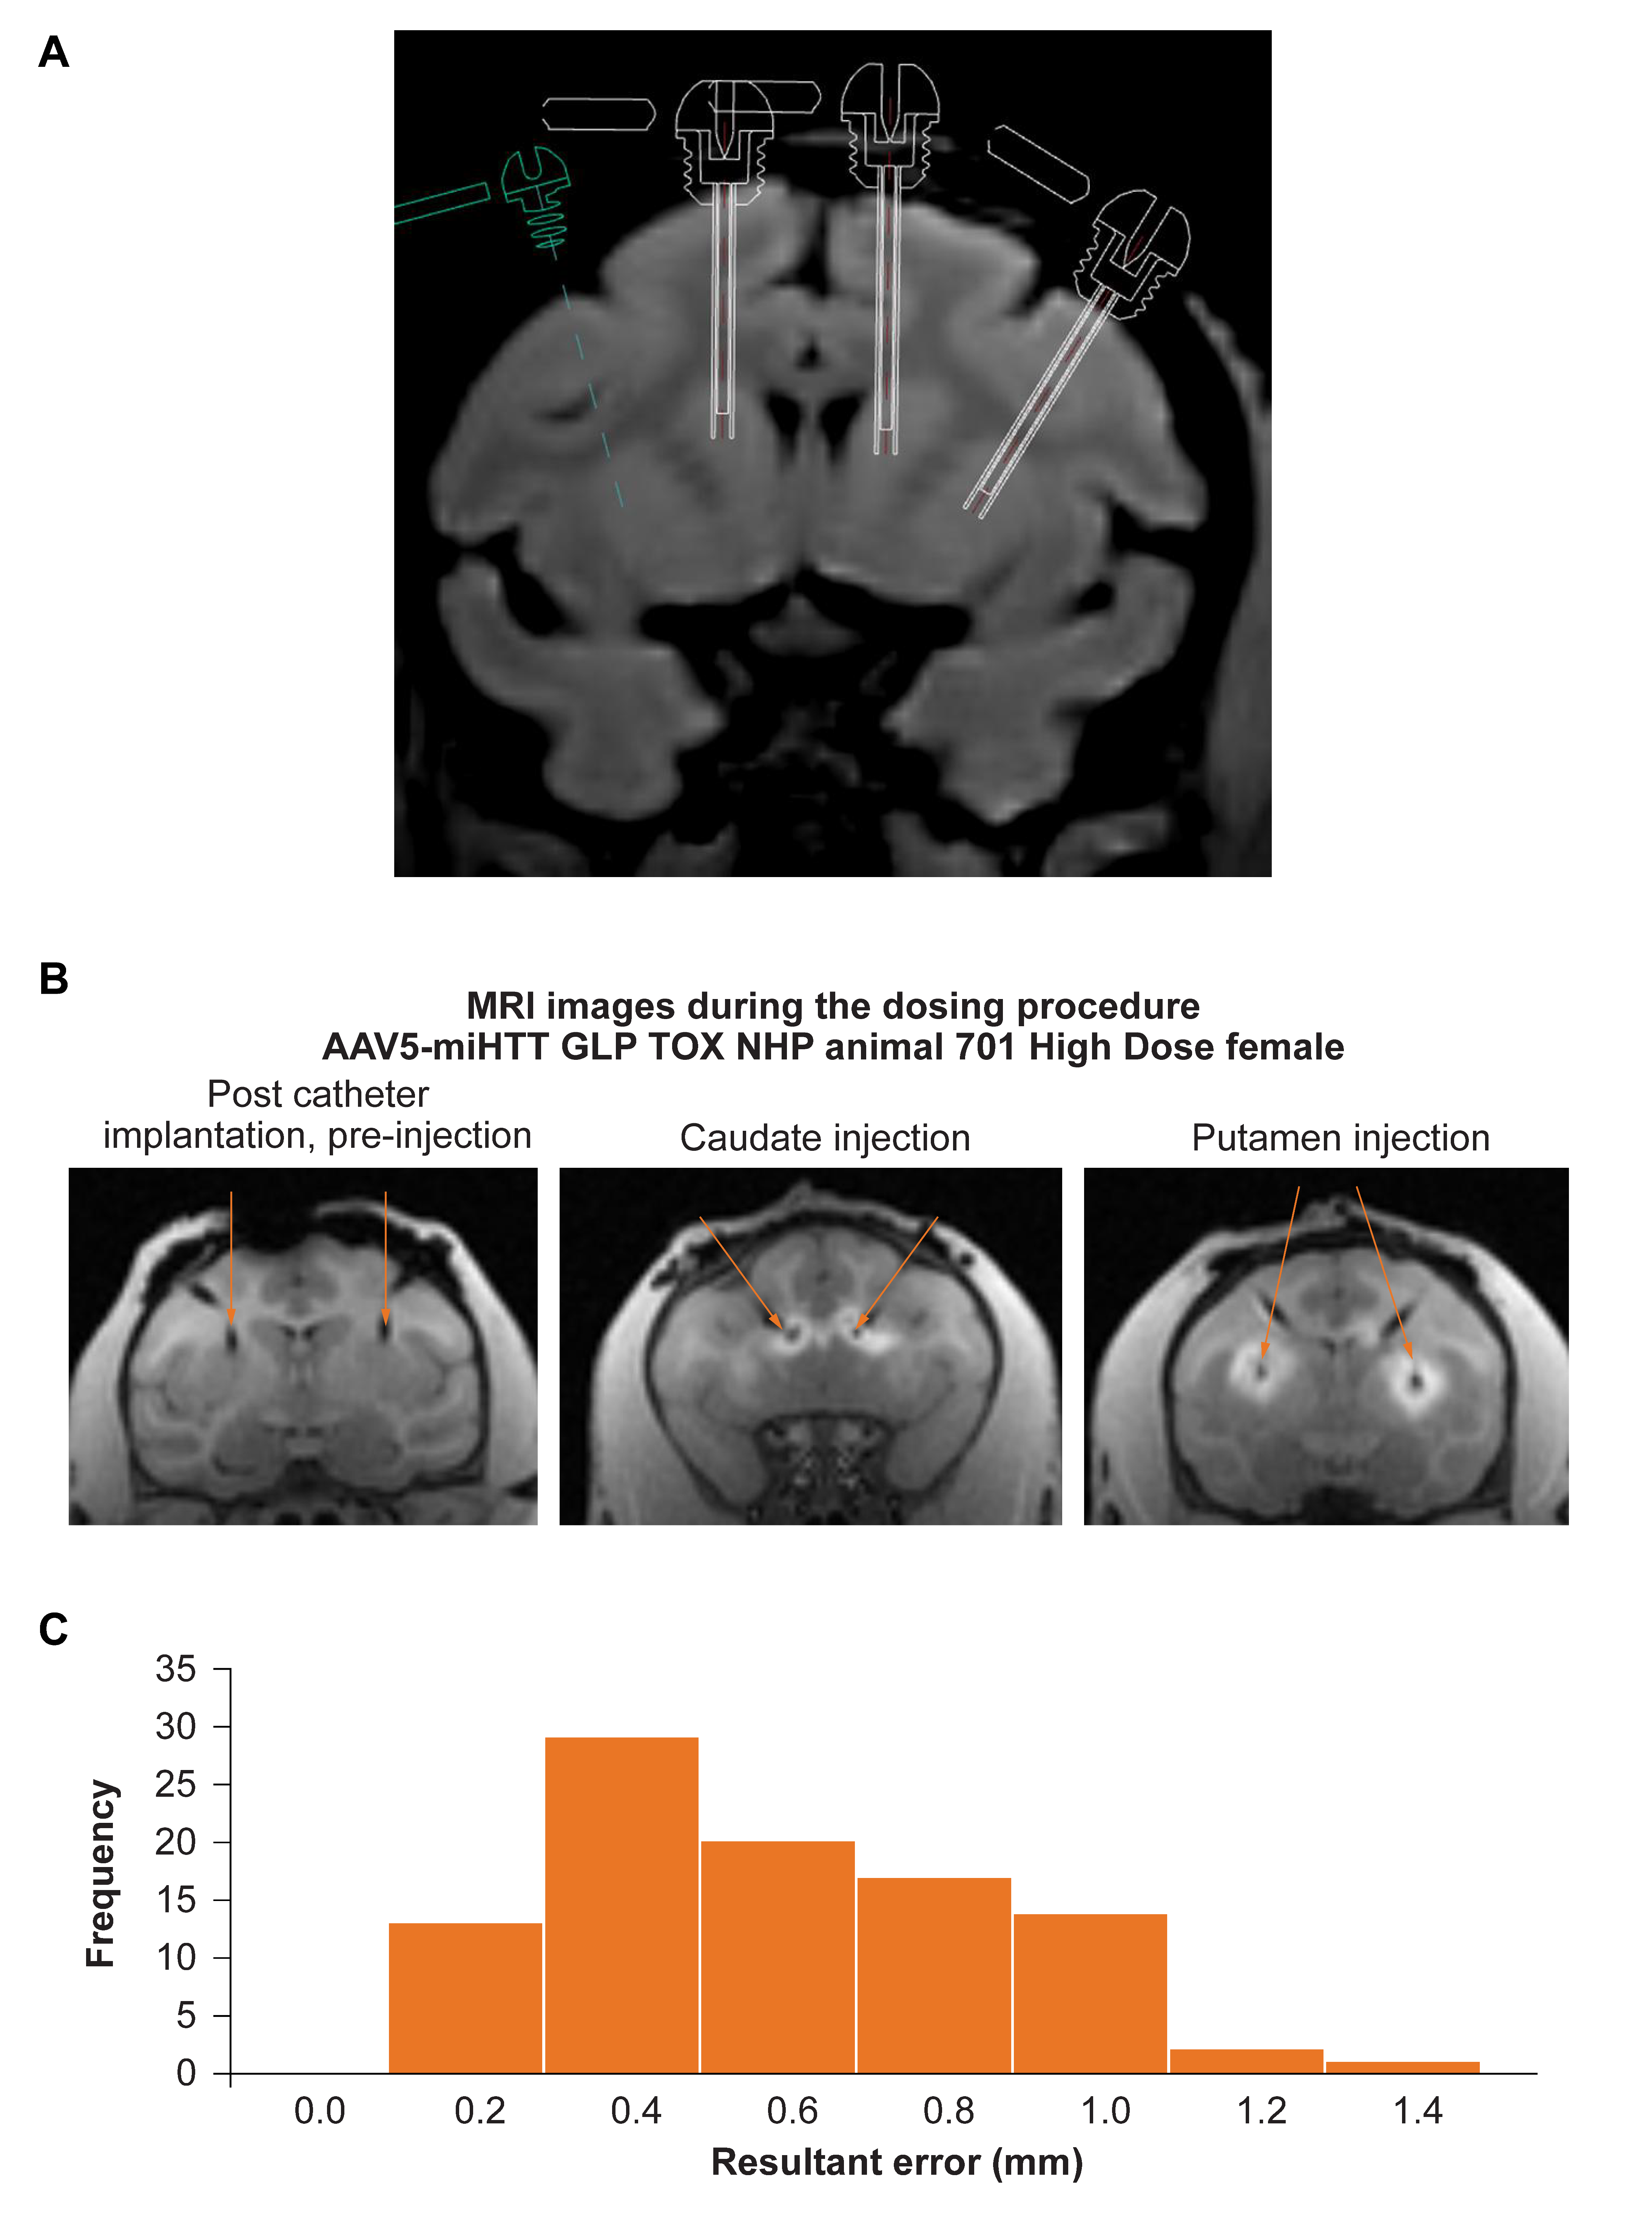

A total of ninety-six catheters were implanted in 24 NHP by MRI guided CED administration of AAV5-miHTT using specialized planning software (Figure 1a). All catheters were successfully implanted into the intended target regions (head of the caudate nucleus and the rostral part of putamen of both hemispheres) (Figure 1b) with an average standard error mean of 0.5 mm ± 0.03 (which is the size of one voxel in the images) and nearly all (97%) catheters were implanted within 1 mm of the planned target, which is well within the accepted range (Figure 1c). The tracer signal to confirm correct placement and injection was present in the target areas in 97% of the injections. The tracer signal was primarily found in the target areas and in most NHPs, distribution of tracer signal was also recorded in other peri-striatal structures (internal capsule, globus pallidus) as well as outside the striatal structures into adjacent structures (e.g., external capsule, corpus callosum and in a few cases into cortical structures). Only in one female NHP in the AAV5-miHTT 2 × 1012 gc group almost no tracer signal was detectable in the left caudate (1 out of 96 injections). The dose completion MRI confirmed accurate placement of the catheters, resulting in an excellent filling of target structures.

Figure 1.

Successful MRI guided convection enhanced delivery of AAV5-miHTT to non-human primates (NHP). (A) The trajectory of the cannulas going into the target brain regions was planned based on individual animal MRI to calculate the exact coordinates of the trajectory. (B) Intra-operative MRI allowed close monitoring of the injections, with the left panel showing catheter placement before the injection (indicated by the orange arrows), and the middle and right panel showing the gadolinium signal of caudate nucleus and putamen being injected, respectively. (C) The error between the planned and actual injection location of all injections was measured based on the gadolinium signal. Nearly all (97%) injections were within 1 mm of the planned location within the target brain area, showing high accuracy. The graph shows how frequently (out of 96 in total) the resultant error of a certain distance was recorded.